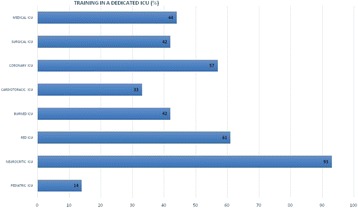

P151 - Ultrasound guided central venous access technique among French intensivists

M. Bastide, J. Richecoeur, E. Frenoy, C. Lemaire, B. Sauneuf, F. Tamion, S. Nseir, D. Du Cheyron, H. Dupont, J. Maizel